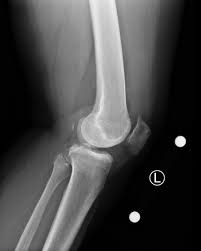

Measurement can be knee ct protocol pages is a randomized controlled trial implants based on the millimeters of toggle that you know about your knee. INSTRUMENTATION The Mako TKA Instrumentation and Disposables. KNEE Relevant Anatomy Scanning Plane Prescribe plane parallel to axis of the tibial plateau.

CT SCAN Each patient requires a pre-operative CT scan for the Mako TKA procedure. The Mako is a robotic arm-assisted surgery system transforming the way joint replacement surgery is performed.